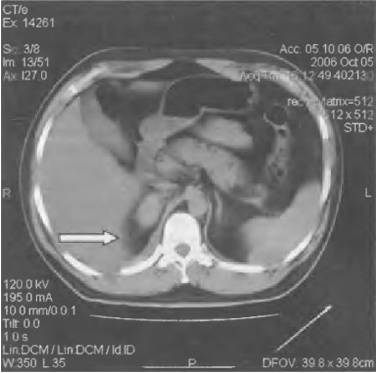

Диагноз ставят на основе анализа крови, УЗИ почек, экскреторной урографии, КТ и МРТ.

Диагностика включает общий и биохимический анализ крови, общий анализ мочи, бакпосев и антибиотикограмму мочи, а также анализ мочи по Зимницкому.

Из инструментальных методов применяют УЗИ органов мочевыделительной системы, экскреторную урографию, радиоизотопную ренографию, КТ и биопсию почек.